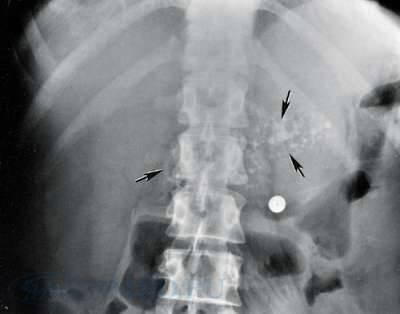

Обзорная рентгенографияверхнего отдела брюшной полости имеет больше академическое значение в диагностике хронического панкреатита, однако характерные изменения удается выявить лишь у больных с выраженным обызвествлением паренхимы железы и/или достаточно крупными обызвествленными конкрементами в панкреатическом протоке.

Типичным рентгенологическим признаком хронического панкреатита является кальциноз железы с характерной локализацией вблизи II поясничного позвонка.

Наиболее частой причиной кальциноза бывает алкоголь, но его причиной могут стать также тяжелая форма белково-калорийной недостаточности питания, гиперпаратиреоз, наследственный и посттравматический панкреатит.

Рис. 1. Рентгенография органов брюшной полости. Определяются множественные кальцификаты в поджелудочной железе, характерные для хронического панкреатита.